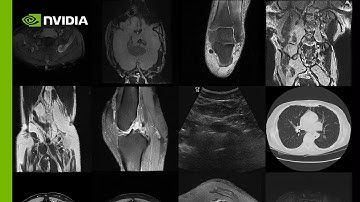

Lemay.ai Machine Vision Demo